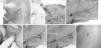

Material y métodosSe modificó el catéter distal tras su uso en 4 especímenes animales. Se diseñó «sobre la guía» (over the wire) y se disminuyó su flexibilidad, y además se agregaron accesorios al equipo. Luego se utilizó en humanos bajo ligeras modificaciones de la técnica de punción yugular. Se evaluaron las complicaciones, el tiempo operatorio y la evolución durante 6 meses.

Material and methodsThe distal catheter was modified after its use in 4 animal specimens. It was designed «over the wire», with its flexibility being reduced and accessories being added. The device was subsequently used in humans, with slight modifications of the jugular vein catheterization technique. We evaluated complications, surgical time and outcome during 6months.